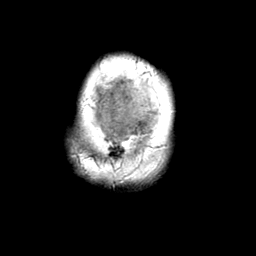

Meningioma, MR Study #1 -- Slice #22

[Home][Help][Clinical] Slice 22